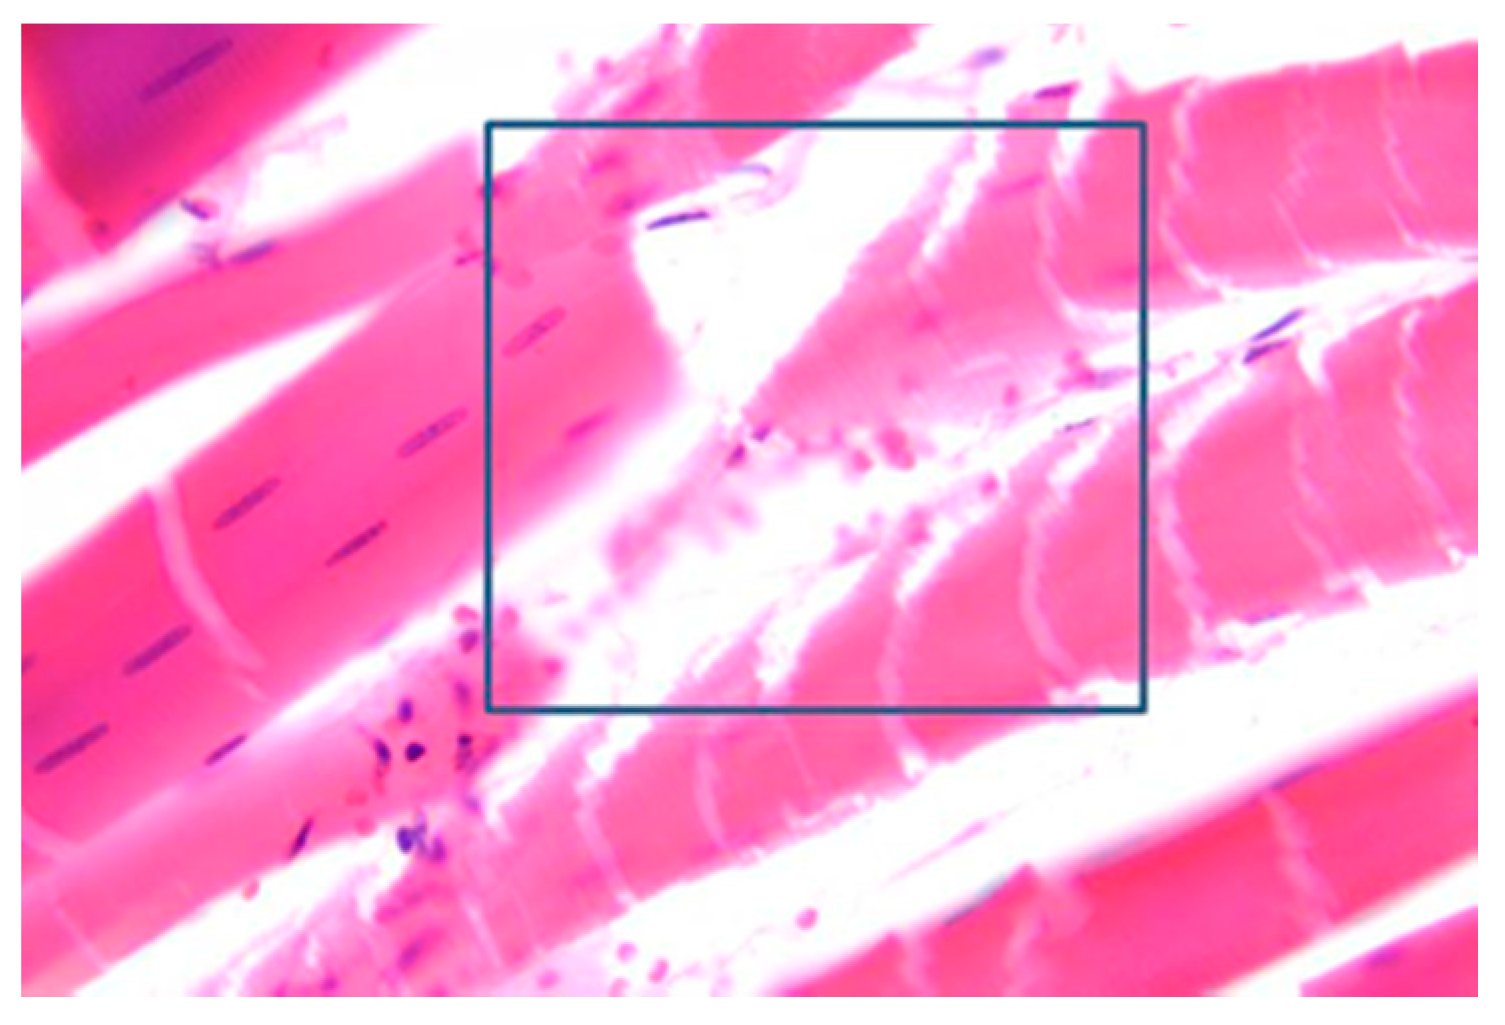

3.5. Muscles Damage

| DeBono, et al. [36] | HV | Muscle fiber fragmentation; red blood cell extravasation; neural damage; |